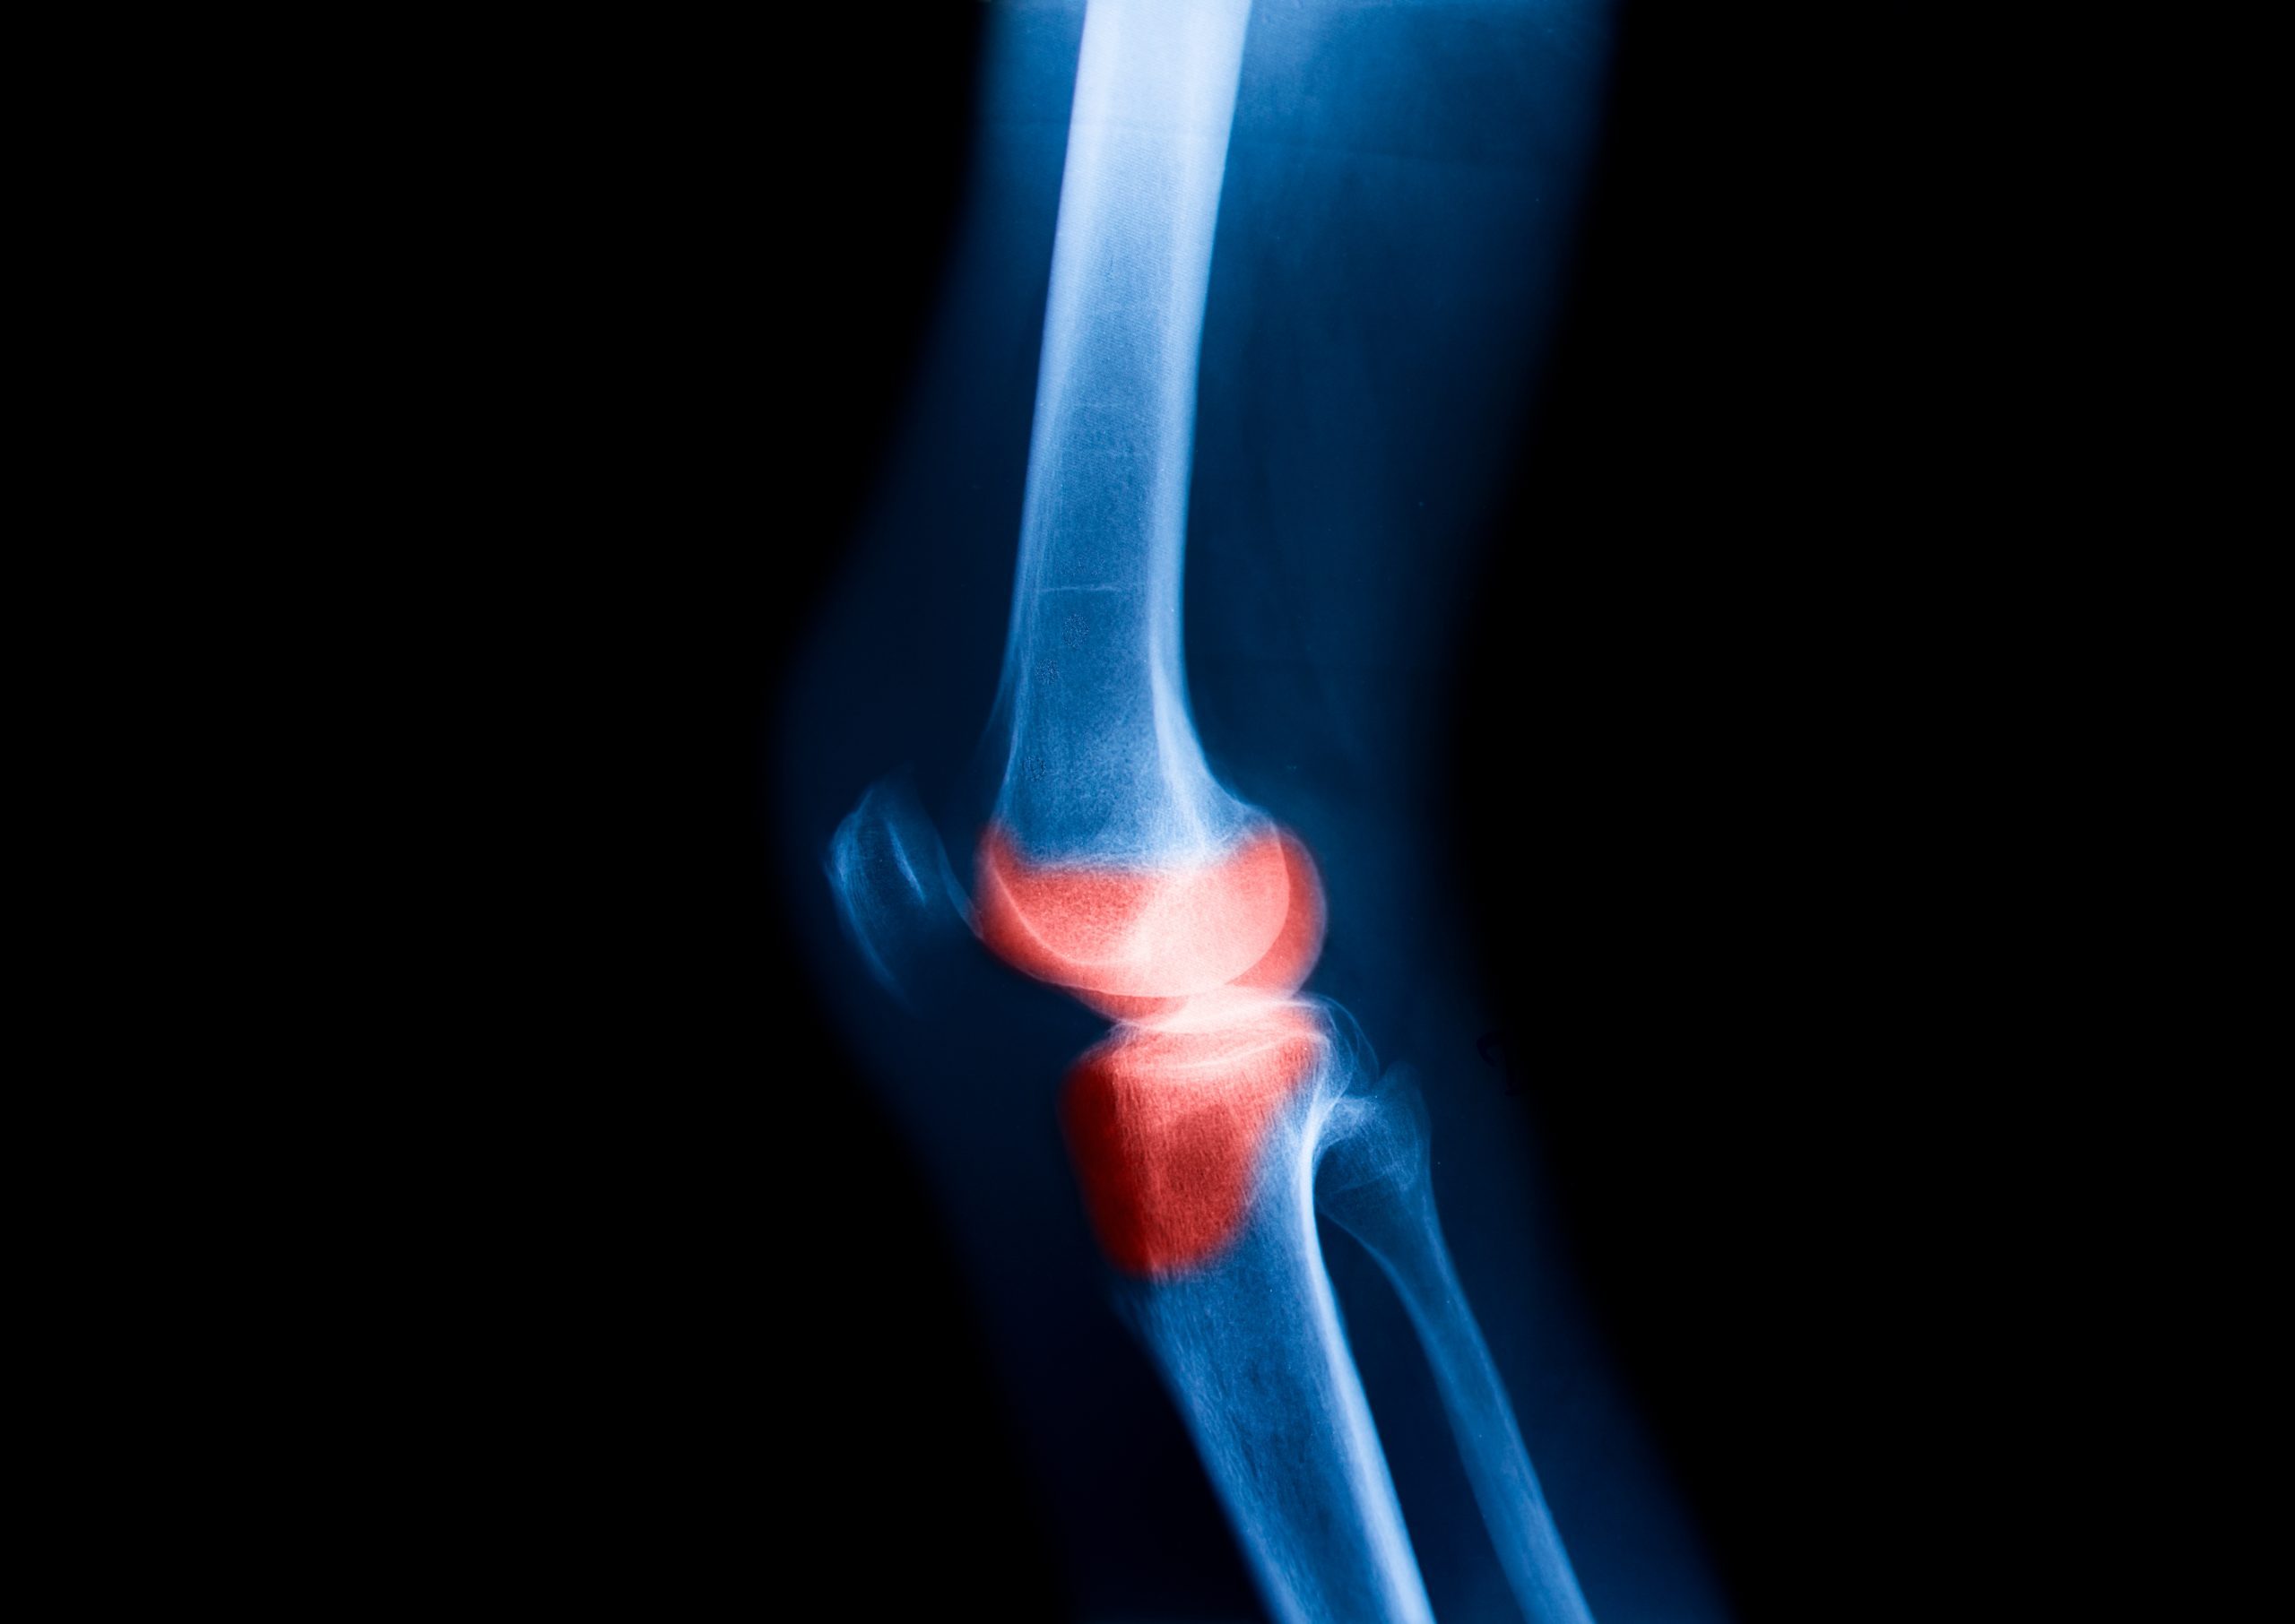

El desgaste de rodilla o artrosis de rodilla es un padecimiento que afecta a personas de todas las edades. Afecta el cartílago, los revestimientos, el hueso, los tendones y ligamentos de la articulación.

El cartílago es un tejido elástico que cubre los extremos de los huesos y permite que las articulaciones se muevan suavemente. En la artrosis de rodilla, este cartílago se desgasta gradualmente, lo que provoca que los huesos rocen entre sí, causando dolor, inflamación y limitación en la movilidad.